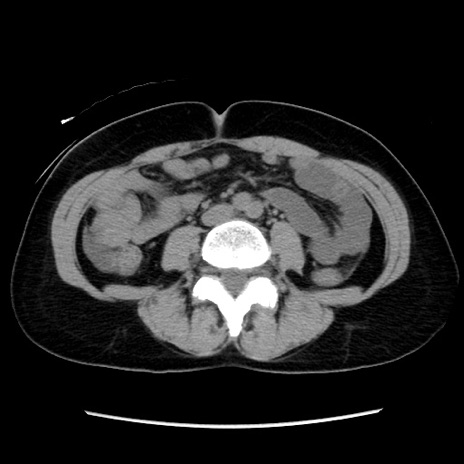

症例10(横断像)

【症例】 50歳代女性

【主訴】 腹痛

【現病歴】前日生レバーを食べた。今朝に排便あり。 昼前に突然発症の腹痛を生じ、当院救急外来を受診した。

【既往歴】 子宮筋腫にてで子宮全摘後

【身体所見】 意識清明、腹部:平坦、軟、下腹部やや左を中心に圧痛・反跳痛あり、筋性防御あり

【データ】WBC 7800、CRP 0.07